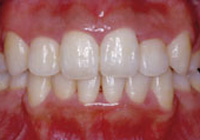

症例1:乱杭歯「歯並びが乱れている」

治療前

治療後